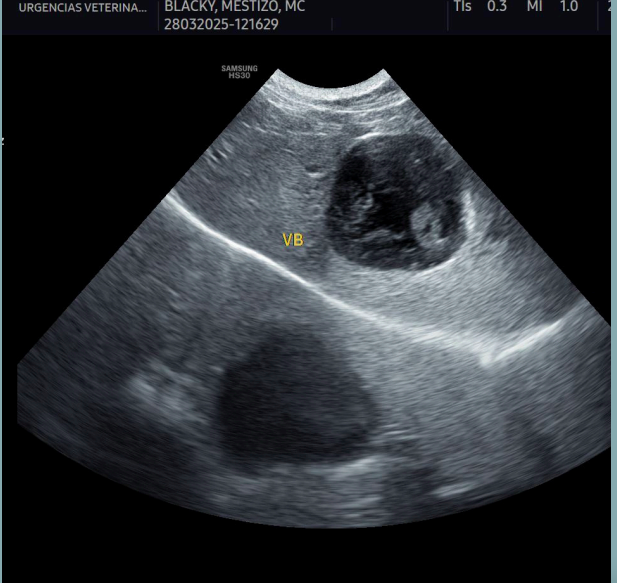

Artefactos: Refuerzo posterior

- Las ondas sonoras pasan a través de un tejido de baja densidad (fluido) y presentan una mayor intensidad respecto a otras ondas en el mismo plano de profundidad.

Artefactos: Sombra de borde

- Se forma en los bordes de estructuras curvas o redondeadas, como un quiste, un vaso sanguíneo o una lesión nodular.

- La imagen muestra una sombra longitudinal a cada lado del borde de la estructura redondeada, debido a la refracción de las ondas en el borde estructural.